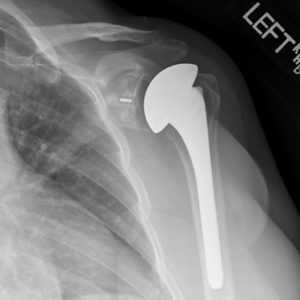

Рентген после эндопротезирования плечевого сустава

- Аппаратные методы в отдаленные сроки предназначены для наблюдения за правильностью положения, глубиной посадки, целостностью протезной конструкции. Они основаны на применении способов рентгенографии.